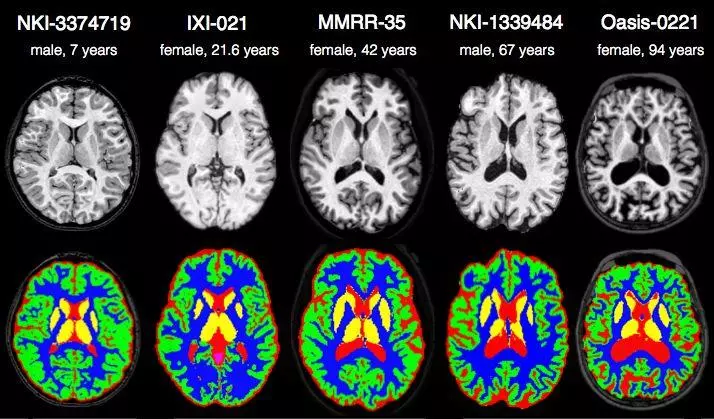

大脑区域及形状个体差异示意图

下面我们以脑区域分割为例,讨论一下该任务的难点,并通过一个应用实例来进一步理解医学图像中的脑区域分割问题。